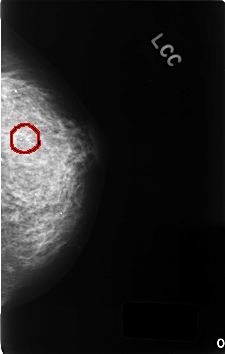

C_0344_1.LEFT_CC

LEFT_CC LINES 4592 PIXELS_PER_LINE 2920 BITS_PER_PIXEL 12 RESOLUTION 50 OVERLAY

FILE: C_0344_1.LEFT_CC.OVERLAY

TOTAL_ABNORMALITIES 1

ABNORMALITY 1

LESION_TYPE CALCIFICATION TYPE FINE_LINEAR_BRANCHING DISTRIBUTION CLUSTERED

ASSESSMENT 5

SUBTLETY 5

PATHOLOGY MALIGNANT

TOTAL_OUTLINES 1

BOUNDARY